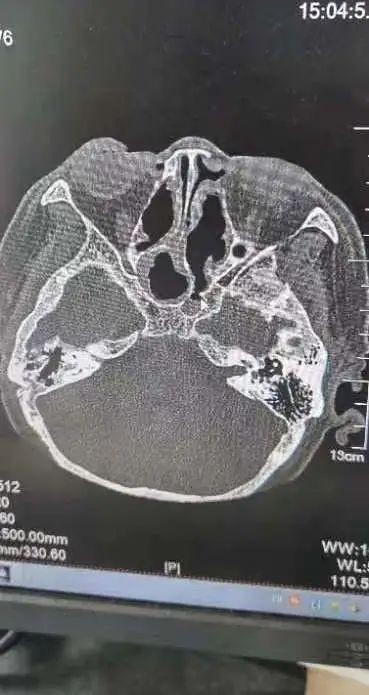

術(shù)前術(shù)后CT對(duì)比

“由于蝶竇位置特殊,位居顱底深部,與垂體、頸內(nèi)動(dòng)脈、視神經(jīng)等重要結(jié)構(gòu)緊密相連,一旦損傷頸內(nèi)動(dòng)脈,將導(dǎo)致大出血,損傷視神經(jīng)則可能造成不可逆的失明。其次,這個(gè)病例具有迷惑性,膿囊腫壓迫的是右側(cè)蝶竇,正常來(lái)說(shuō)是右眼無(wú)光感,但實(shí)際上是左側(cè)視力失明,鼻竇CT雖然能看到占位,但是看不到蝶竇膿囊腫侵蝕破壞的地方。”王浩臨危不亂,在鼻內(nèi)鏡下精細(xì)操作,探查發(fā)現(xiàn),由于右側(cè)巨大腫物擊穿蝶竇間隔進(jìn)而造成左側(cè)視神經(jīng)管受損而導(dǎo)致左眼失明,手術(shù)全程順利,術(shù)后予以抗感染、止血等治療,岳老太頭痛等癥狀消失,左眼復(fù)明。一周后出院時(shí)向耳鼻喉科醫(yī)護(hù)人員豎起了大拇指,為他們精湛的醫(yī)術(shù)與貼心的護(hù)理服務(wù)點(diǎn)贊。